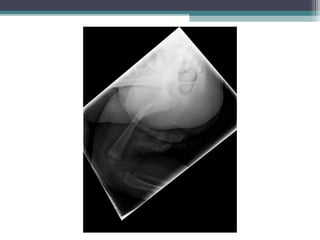

 Acude a urg hospital de zona por fractura femoral.

 Traslado e ingreso en hospital de referencia con

servicio de traumatología infantil para reducción

bajo anestesia. Seguimiento en consulta de COT allí

▫ 2 meses: fractura femoral